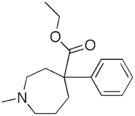

Phenylpiperidines

- Pethidine (meperidine)

The first fully synthetic opioid was meperidine (later demerol), found serendipitously by German chemist Otto Eisleb (or Eislib) at IG Farben in 1932.[228] Meperidine was the first opiate to have a structure unrelated to morphine, but with opiate-like properties.[199] Its analgesic effects were discovered by Otto Schaumann in 1939.[228] Gustav Ehrhart and Max Bockmühl, also at IG Farben, built on the work of Eisleb and Schaumann. They developed "Hoechst 10820" (later methadone) around 1937.[230] In 1959 the Belgian physician Paul Janssen developed fentanyl, a synthetic drug with 30 to 50 times the potency of heroin.[211][231] Nearly 150 synthetic opioids are now known.[228]